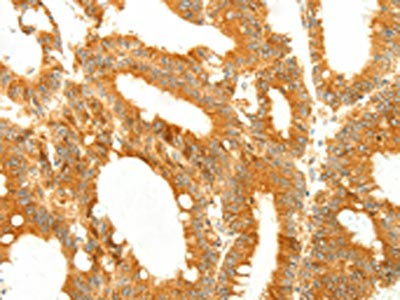

The image on the left is immunohistochemistry of paraffin-embedded Human colon cancer tissue using CSB-PA966330(DIABLO Antibody) at dilution 1/50, on the right is treated with fusion protein. (Original magnification: ×200)